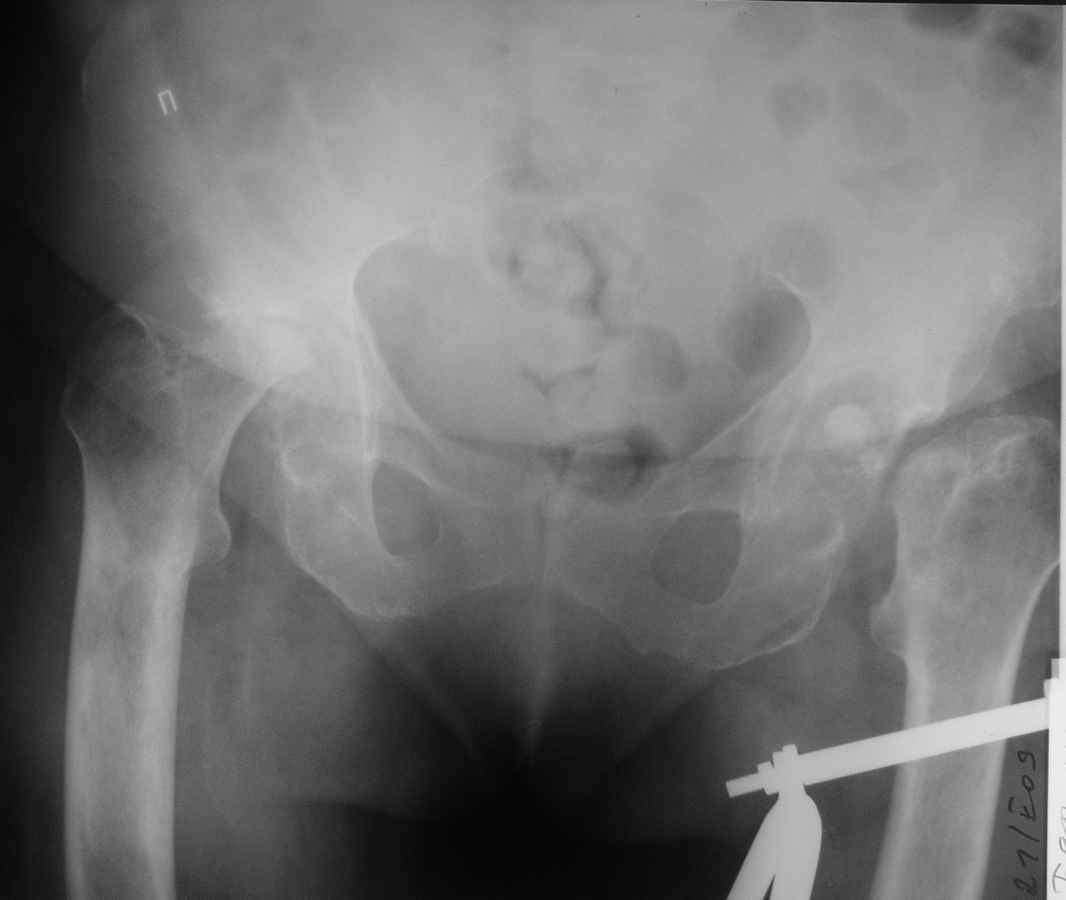

Здравствуйте уважаемые коллеги. Поступила женщина 60 лет с переломом

левого бедра в н/3 диафиза, травма произошла около 2-х недель назад,

упала дома. При сборе анамнеза установлено, что в течении 3-х

последних лет больную беспокоили боли в тазобедренных суставах, и уже

около 1,5 лет она передвигается только на сидячей каталке. При

дополнительном обследовании выявлена данная рентгенологическая

картина. Факт какой-либо травмы отрицает, поражения мелких и средних

суставов кистей и стоп нет, в анализе крови СОЭ 60мм/ч, лейкоцитоза

нет. Помогите, пожалуйста, определиться с диагнозом, какие

исследования необходимо провести.

По тактике лечения планируем интрамедуллярный остеосинтез левого

бедра, эндопротезирование тазобедренного сустава справа. После

сращения бедра эндопротезирование левого тазобедренного сустава.